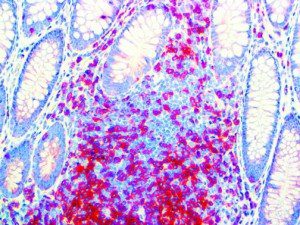

The first cytokines released are interleukin 1β (IL-1β) and tumor necrosis factor-α (TNF-α), which attract a variety of circulating white blood cells (WBCs) to the infection site, including neutrophils, monocytes, macrophages, and natural killer (NK) cells. This response, along with the antipathogenic chemicals released by these cells (i.e., complement), comprise the innate immune response. These cells directly attack the invading pathogen and also release additional cytokines, chief among them interleukin-1 and 6 (IL-6). IL-6 is essential for invoking the adaptive immune response, which calls T-cells, B-cells, and T helper (Th) cells to the infection site. IL-6 also stimulates further recruitment, proliferation and activation of macrophages.

This activation induces inflammatory monocytes to highly express IL-6, starting a localized and then systemic cascade effect that results in hyperproduction of IL-6, which accelerates the inflammatory process. Because IL-6 also increases vascular permeability, excessive levels cause blood vessels to become very leaky. This, along with clotting factors released from vascular endothelial cells, stimulates the coagulation cascade, resulting in microthrombosis (tiny clots), which leads to ischemia and tissue death of the kidney, intestines, heart, liver, brain and extremities.